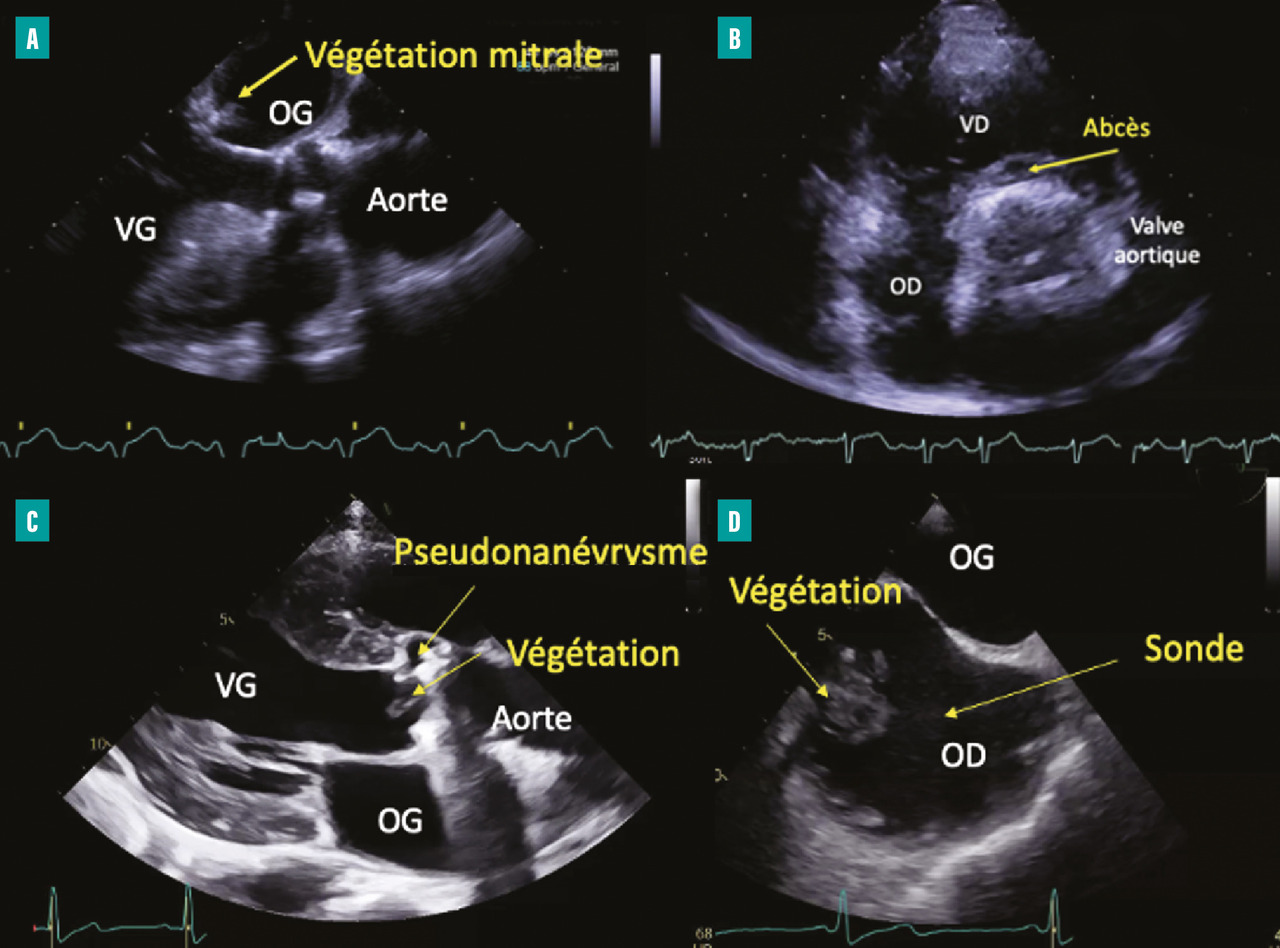

– la végétation (lésion valvulaire la plus fréquente, image vibratile insérée sur une valve ou sur toute structure endocardique ou du matériel intracardiaque correspondant à une masse septique) ;

– les lésions périvalvulaires :

• abcès (épaississement périvalvulaire hyperéchogène, puis néocavité vide d’écho),

• pseudoanévrysme avec déhiscence d’une prothèse (espace anéchogène périvalvulaire pulsatile communiquant avec les cavités d’amont et d’aval et responsable d’une fuite périprothétique),

• communication de type fistule entre deux cavités adjacentes et perforation valvulaire (fig. 1 ).

La taille d’une végétation (longueur maximale de la végétation) est une mesure essentielle guidant la prise en charge chirurgicale.

Dès la suspicion clinique d’EI, une échocardiographie transthoracique (ETT) doit être systématiquement réalisée. Les anomalies échocardiographiques principales amenant au diagnostic sont :– la végétation (lésion valvulaire la plus fréquente, image vibratile insérée sur une valve ou sur toute structure endocardique ou du matériel intracardiaque correspondant à une masse septique) ;

• communication de type fistule entre deux cavités adjacentes et perforation valvulaire (